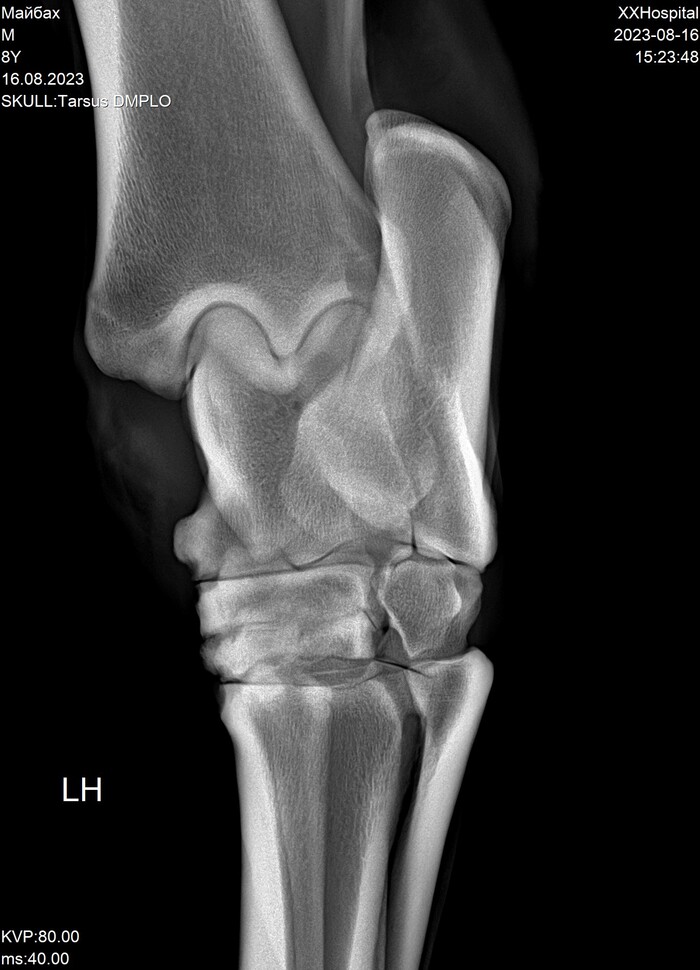

На этих x-ray снимках Домбай.

У него артроз (или артрит, я такой себе врач) пальчиков на руках.

Плюс косточка в копыте подходит очень близко к краю.